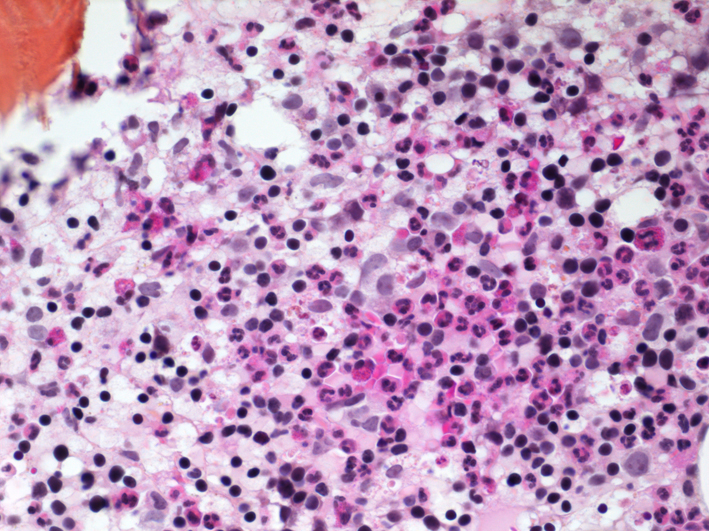

APL is a hematopoietic neoplasia of the acute myeloid leukemia (AML) group. This disorder is characterised by an excess of atypical promyelocytes in the bone marrow and peripheral blood. The cytogenetic anomaly t(15:17) is a classic finding and is used for diagnostic confirmation of APL according to the WHO classification system of AML [8]. This translocation induces a fusion between promyelocytic leukemia (PML) gene and retinoic acid receptor alpha (RARalpha) gene creating a PML-RARalpha gene inducing excessive medullary production of promyelocytes through a PML-RARalpha protein. Five to twenty percent of AML cases are classified as APL [9]. The natural evolution of APL is very aggressive with median survival of less than 1 month, but recent advances in therapy with combined treatment of ATRA and arsenic provide excellent response with complete remission up to 90-95% of patients [10]. By binding to RARalpha moiety of the PML-RARA oncoprotein, ATRA leads to differentiation from promyelocytic malignant cells to mature neutrophils while arsenic binds to the PML moiety and induces apoptosis and partial differentiation of the promyelocytes cells [11, 12].